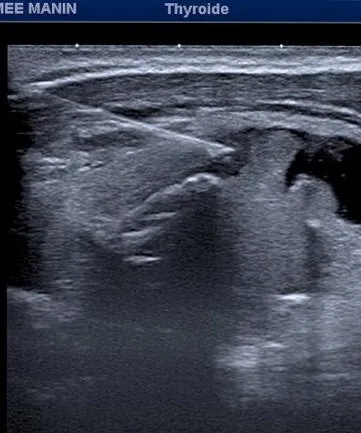

Sous Guidage Échographique : Prélèvement de cellules d'un nodule thyroïdien à l'aide d'une aiguille fine pour une analyse cytologique, déterminant la nature bénigne ou maligne du nodule.

Le geste est effectué sous contrôle visuel continu (Écho ou Scanner) pour une précision maximale.